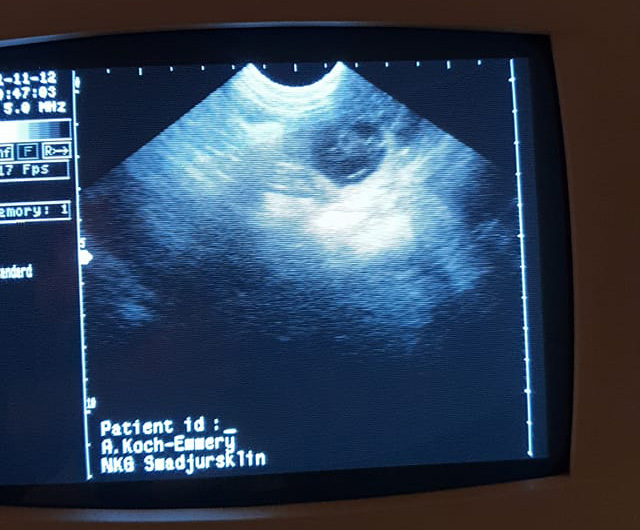

Stina är dräktig :)

Om allt går som det ska föds det några få ( vi såg bara 2 st ) valpar i mitten av december. Håller tummarna för att allt ska gå bra och att det blir betydligt fler än de vi såg.